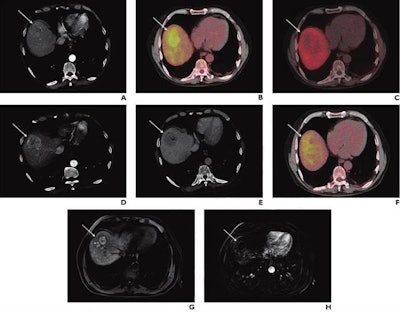

French researchers looked at how patients with hepatocellular carcinoma (HCC) responded to TARE on PET/CT imaging early after treatment using either FDG or an experimental radiotracer called F-18 fluorocholine (FCH). Early PET/CT with either tracer could predict early responses to treatment, as well as patients' overall survival, they found.

In this study, the researchers tested whether the early use of PET/CT with FDG or F-18 FCH radiotracers could predict treatment response after six months as well as overall survival rates in HCC patients after TARE.

Of the 37 patients, 15 (41%) exhibited an early post-treatment PET/CT response based on imaging with at least one of the two tracers, the researchers found. A response at one month (based on mRECIST) was observed in 10 (29%) of 35 patients. Twelve (52%) of 23 patients exhibited an mRECIST response at six months.